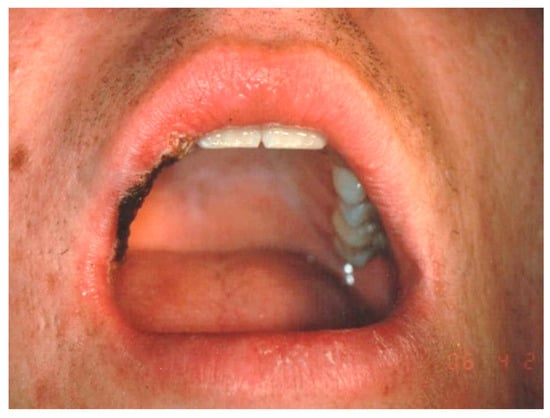

Aesthetic Treatment Outcomes of Capillary Hemangioma, Venous Lake, and Venous Malformation of the Lip Using Different Surgical Procedures and Laser Wavelengths (Nd:YAG, Er,Cr:YSGG, CO2, and Diode 980 nm)

2.2. Participants